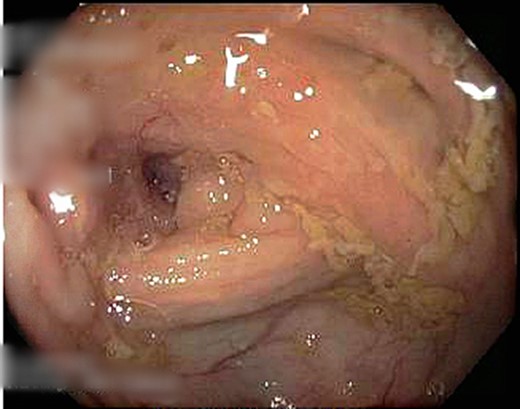

A 69-year-old otherwise well female with no prior history of malignancy underwent colonoscopy for investigation of upper abdominal pain, altered bowel habits—looser, more frequent stools—and subacute weight loss of 8 kg over a number of years. At colonoscopy, luminal narrowing, the impression of colonic thickening and very poor distension was encountered at the ascending colon (Fig. 1). The colonoscope was unable to traverse the narrowed segment. The remainder of the colon was unremarkable and there was no evidence of diverticulosis. Given the normal appearance of the mucosa at the area of presumed pathology, deep biopsies were taken using a bite-on-bite technique in order to ensure that submucosa was captured in the sample. Upper endoscopy was also performed and was normal.